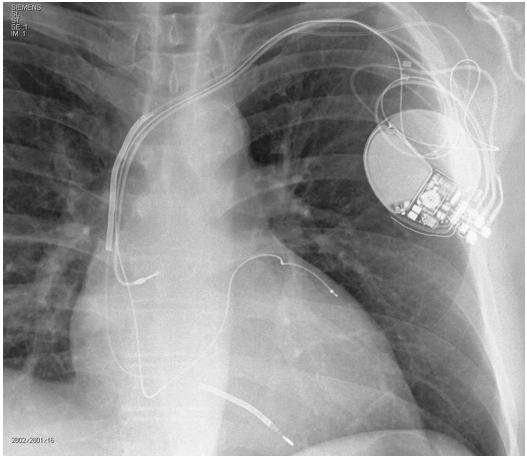

Considere:

• FEVE: Fração de ejeção do ventrículo esquerdo • NYHA: Classe funcional de insuficiência cardíaca da New York Heart Association • BRE: Bloqueio de ramo esquerdo • BRD: Bloqueio de ramo direito

Em pacientes com insuficiência cardíaca sem história de arritmias ventriculares ou síncope, assinale a opção que preencheria critérios para implante do dispositivo presente nessa radiografia.